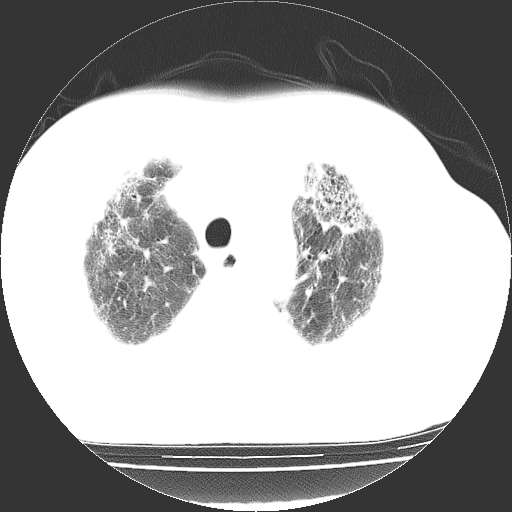

男,68岁,咳嗽、胸闷、发烧三天,查体:双肺散在湿罗音。

首先考虑特发型肺间质纤维化;两侧少量胸腔积液。

依据:1、两肺广泛条索状、网格状、蜂窝状改变。

双肺多发条索状、网格状及小灶状密度增高影。考虑慢支合并感染.间质纤维化,双侧少量胸腔积液

两肺广泛条索状、网格状、蜂窝状改变。肺间质纤维化,肺心病,双侧胸腔积液